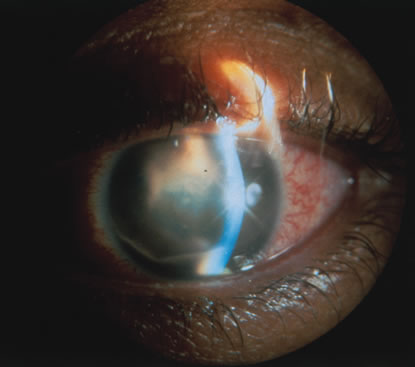

In primary ocular HSV infections, a severe follicular conjunctivitis with regional adenopathy is present. Vesicles may appear on the eyelid skin or lid margin, producing blepharitis (Fig. 3). Corneal involvement initially takes the form of a superficial punctate keratitis, which may progress to dendritic or geographic ulceration. Stromal infiltrates and uveitis are less common and relatively mild in primary disease. In uncomplicated cases, lesions usually heal completely in 2 to 3 weeks without scarring. Most cases of ocular HSV are recurrences. Recrudescent ocular herpes may take the form of dendritic or geographic ulcers, recurrent erosions, interstitial or disciform stromal keratitis, and anterior uveitis.3 HSV may also be an agent of retinitis and acute retinal necrosis (Fig. 4).